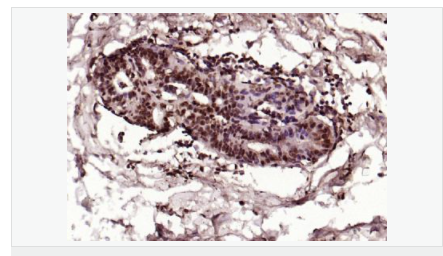

| 產(chǎn)品應用 | ELISA=1:5000-10000 IHC-P=1:100-500 IHC-F=1:100-500 Flow-Cyt=1μg/Test ICC=1:100 IF=1:100-500 (石蠟切片需做抗原修復) not yet tested in other applications. optimal dilutions/concentrations should be determined by the end user. |